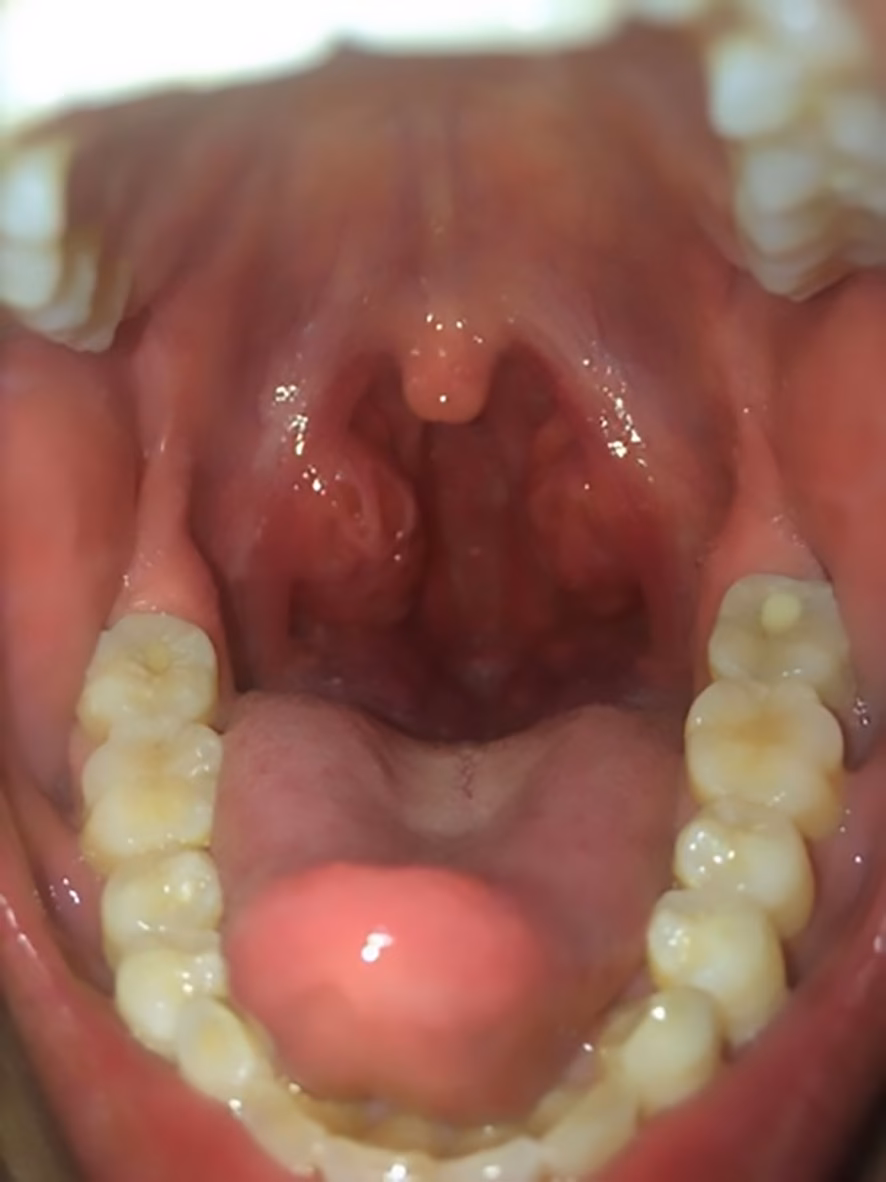

Symptomerne på en F. necrophorum-infektion kan ligne dem fra andre bakterielle halsbetændelser, hvilket gør diagnosen vanskelig alene baseret på symptomer. Typiske tegn inkluderer:

- Kraftige halssmerter, der forværres over flere dage.

- Høj feber.

- Hævede og betændte mandler, ofte med belægninger (pus).

- Hævede lymfeknuder på halsen.

- Hovedpine og generel utilpashed.

Den Alvorlige Komplikation: Lemierres Syndrom

Den primære grund til, at F. necrophorum skal tages alvorligt, er dens potentiale til at forårsage den sjældne, men livstruende tilstand kendt som Lemierres syndrom. Dette syndrom, også kaldet "den glemte sygdom", opstår, når bakterien spreder sig fra den primære infektion i halsen til den store halsvene (vena jugularis interna).